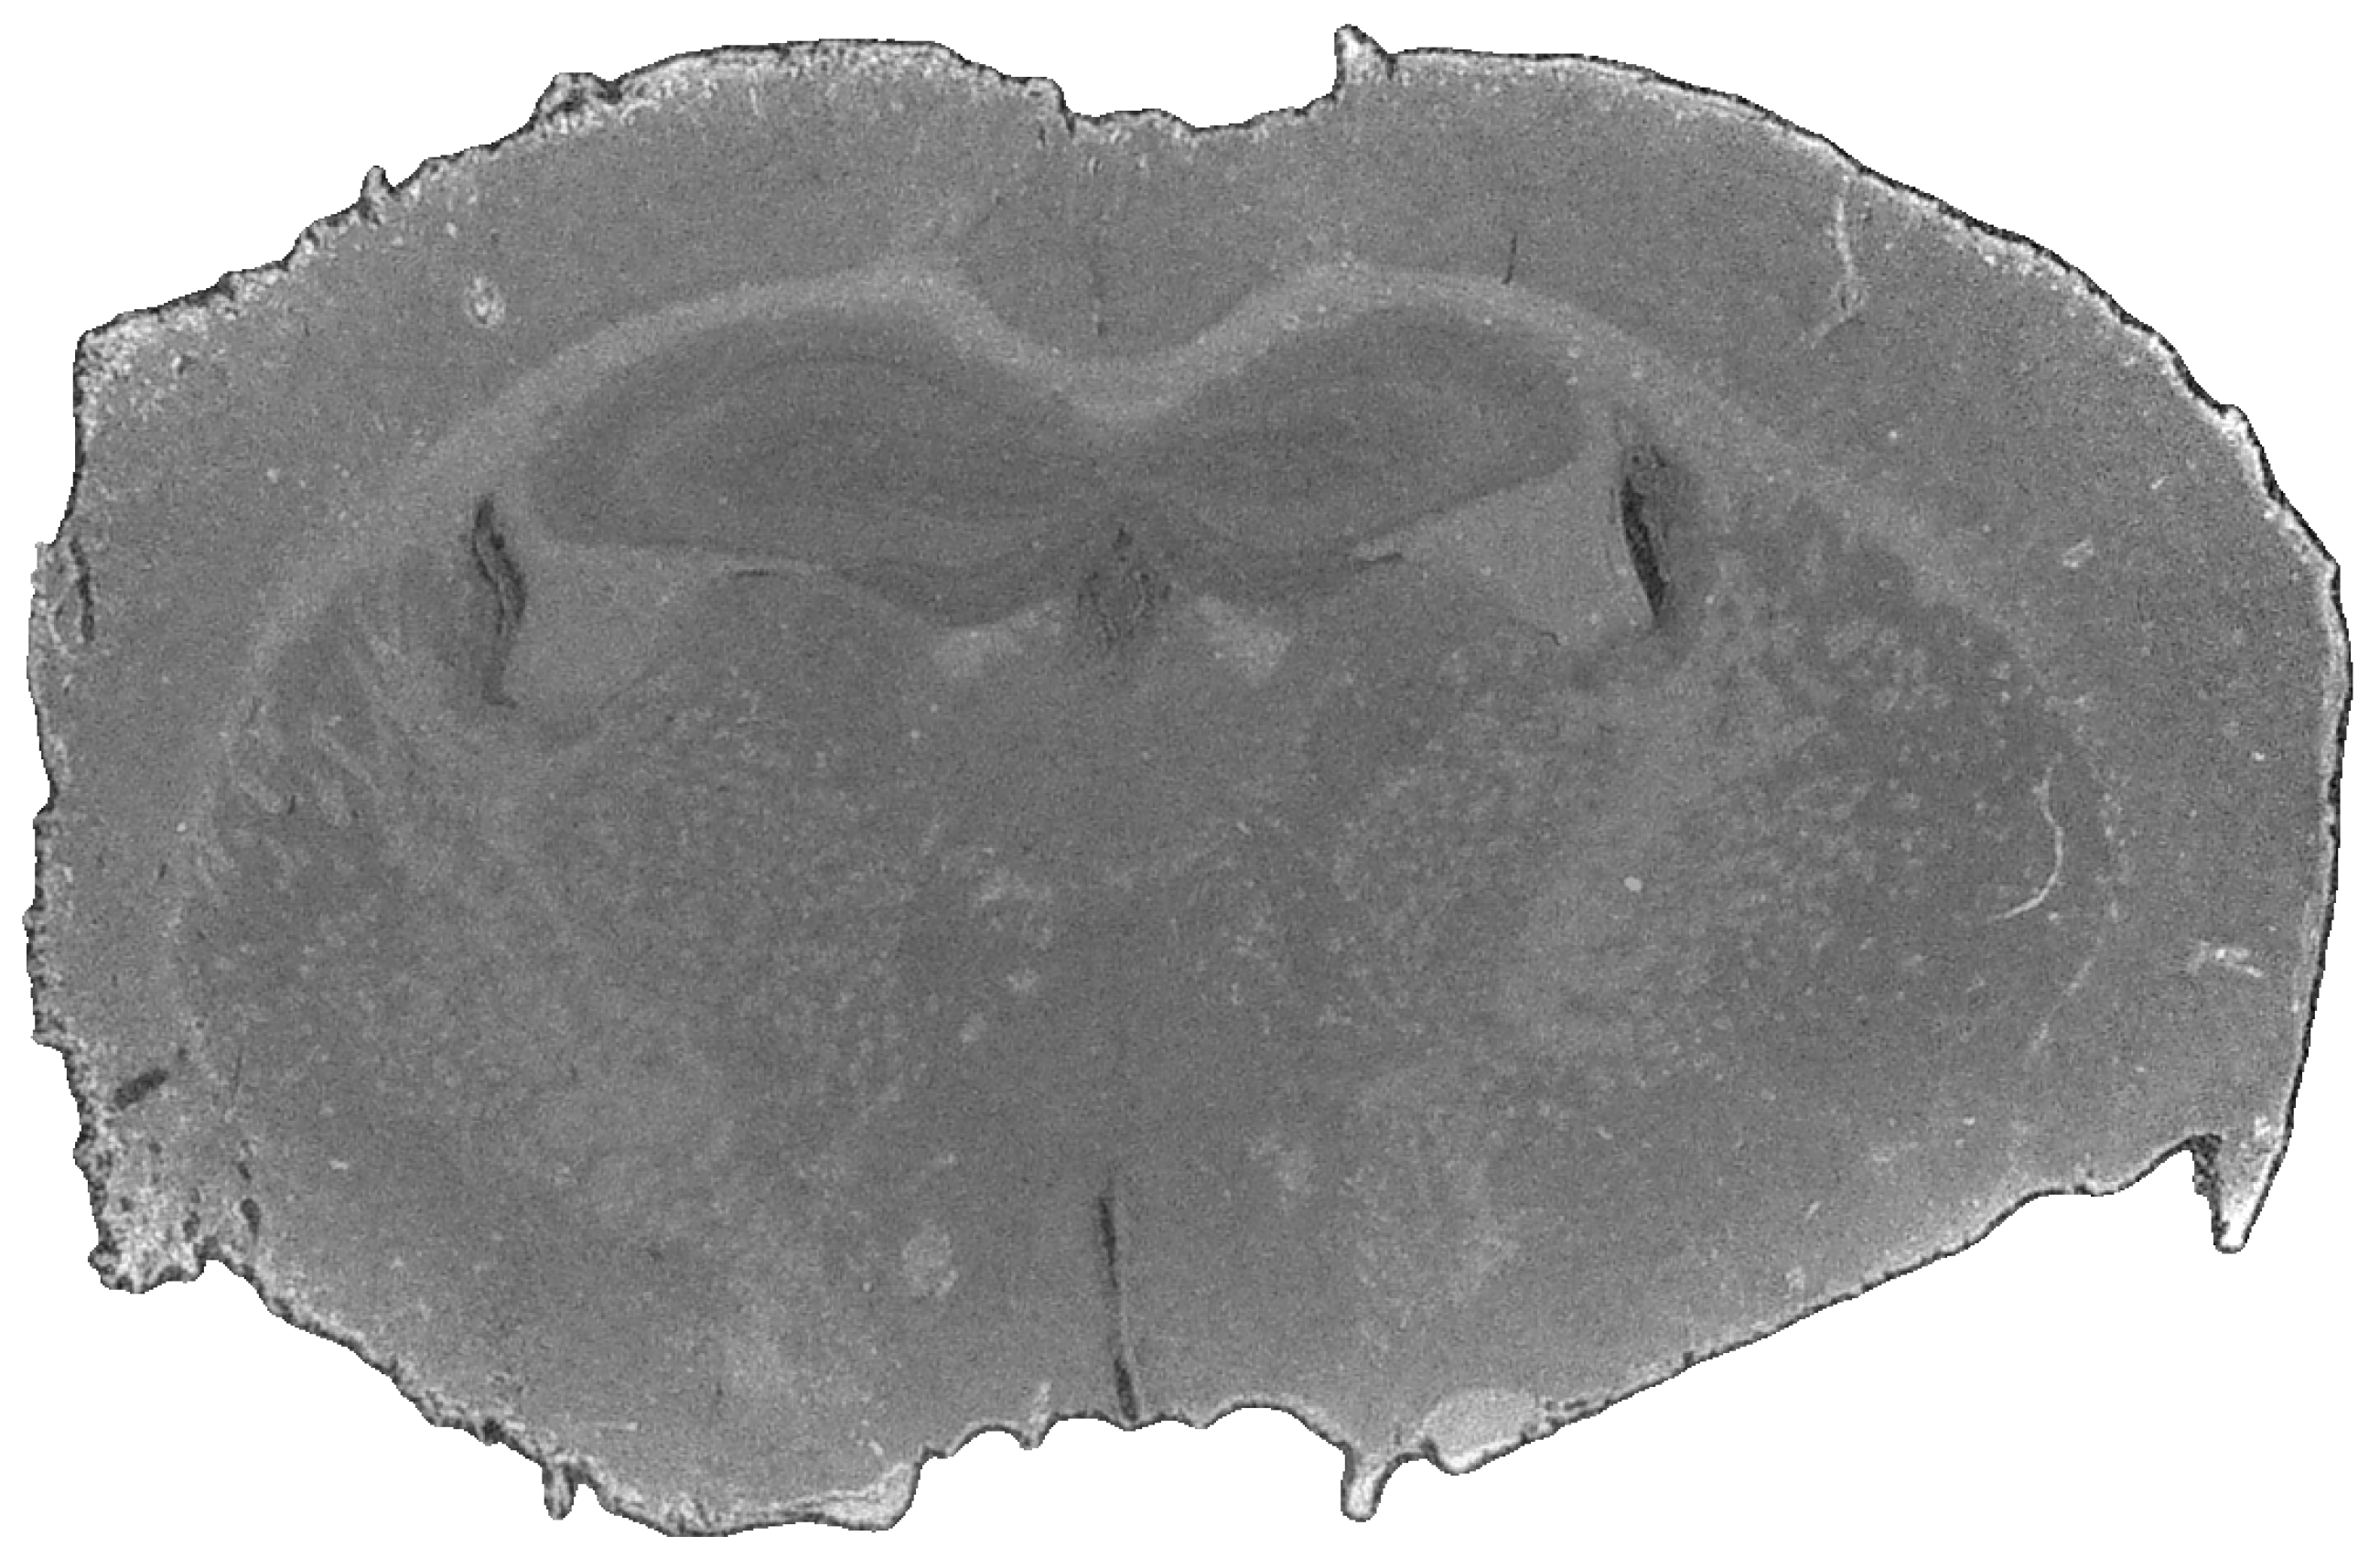

2.2. Data Acquisition

For this study, the pipeline was evaluated using two in-house-developed scanning systems, a near-infrared (NIR) scanner [20] and a laser-based mid-infrared (MIR) scanner [51], representing complementary spectral ranges. Fourier transform infrared (FTIR) imaging, while commonly used as a standard approach in biomedical MIR analysis, was not considered due to its comparatively long acquisition times [51]. Additionally, an RGB reference image (Figure 3) was acquired using a Keyence VHX-7000 microscope at 20× magnification. The RGB modality was limited to a single-shot acquisition even though the system supported image stitching.

Figure 3. Mouse brain slice after with preprocessing, scanned with a Keyence VHX-7000 microscope (Keyence Deutschland GmbH, Neu-Isenburg, Germany) at 20× magnification.